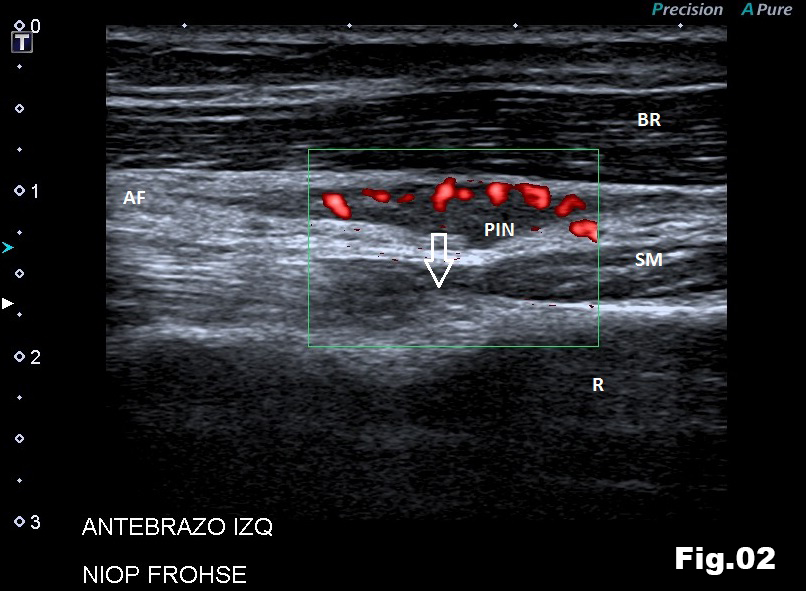

A 51-years-old healthy female, with no history of upper limb injuries, complained of an anterior and proximal left forearm tenderness associated with weakness of the extensor muscles of the forearm. An ultrasound scan was performed and demonstrated a thickened and hypoechoic posterior interosseous nerve (PIN) at the arcade of Frohse, with hypervascularization of the perineurium. In its deeper aspect, there was a subtle irregularity of the radial metaphysis (Fig1,2). The plain film showed a sessile irregularity of the anterior region of the metaphysis (Fig 3). Unenhanced MRI and CT scan were also performed. The CT scan showed the irregularity of the radius (Fig 4) and in the MRI (Fig 5), it was reported as an osteochondroma like metaphyseal lesion of the radius. Initial treatment included a corticosteroid injection around the PIN, but without decrease of symptomatology. The orthopedic surgeon then proceeded with an osteochondroma resection to release the PIN. The upper limb surgical team performed the surgery (Fig 6), and they found a thickened, hyperaemic PIN, adjacent to the osteochondroma (Fig 6,7). They resected the osteochondroma and debrided the PIN (Fig 8). The patient recovered full muscular strength and the tenderness progressively disappeared.

This case report illustrates that evaluation of the PIN, Arcade of Frohse, and radial recurrent artery are very dificult with standard elbow MRI, because small structures (diameters below 5 mm) are beyond the resolution of MRI typically using fields of view (FOV) of 12,0 x 18,6 cm and slice thickness of 3 mm.

With these parameters, obtaining a well defined image of a small structure is almost impossible. However, high frequency ultrasound scans allow high resolution imaging and assessment of these small structures. Furthermore, Power and color Doppler is also a useful adjunct to evaluate the perineural vascularisation.

Fig 2: Ultrasound long axis view of the AF (Arcade of Frohse), showing a swelled PIN and its anatomical relationship with the radius osteochondroma (arrow). SM (Supinator Muscle), BR (Brachioradialis muscle) and R (Radius metaphysis).